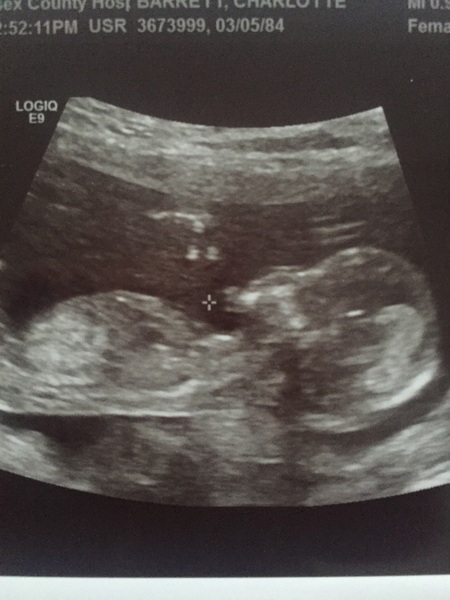

duck what a gorgeous scan picture!